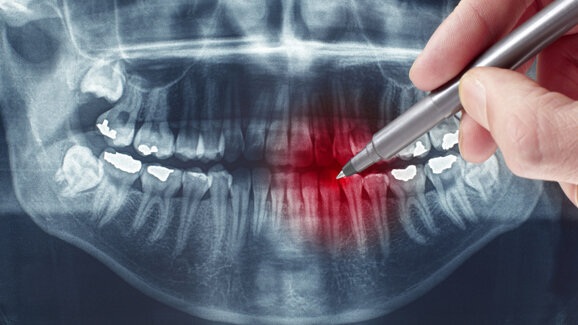

Neben der verbesserten Diagnostik erlaubt der Einsatz von Biomarkern auch eine optimierte Überprüfung des Behandlungserfolges bei Knochenerkrankungen. „Neben der Kontrolle des Behandlungserfolges kann auch die Behandlungstreue durch die PatientInnen überprüft werden, wie etwa die regelmäßige Einnahme von Medikamenten“, beschreibt Barbara Obermayer-Pietsch wichtige Vorteile des Biomarkereinsatzes. Durch die permanente Kontrolle können allfällige Änderungen in der Medikation bzw. Nachjustierungen in der Behandlung bereits lange vor der Anzeige durch bildgebende Verfahren veranlasst werden. „Teilweise werden Veränderungen erst nach Jahren im Röntgenbild oder der Knochendichtemessung sichtbar. Der Einsatz von Biomarkern kann Veränderungen zeitnah anzeigen“, so die Expertin der Med Uni Graz.